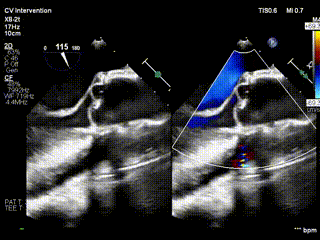

视频3:病例2术前心超提示大量主动脉瓣反流

视频4:病例2术后无反流